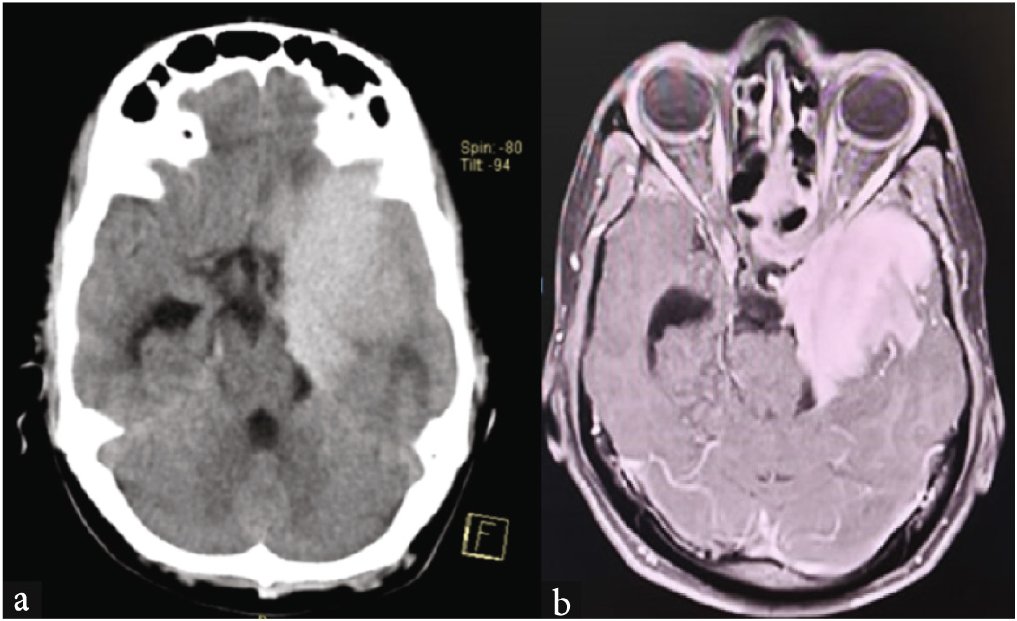

The patient’s MRI brain revealed extensive leukoencephalopathy involving the frontoparietal white matter [Figure 1a] and deep gray matter nuclei [Figure 1b], suggestive of metachromatic leukodystrophy (MLD). The patient was switched to trihexyphenidyl and olanzapine, which led to significant improvement in his symptoms. This case highlights the importance of considering neurological causes like leukodystrophy when psychiatric symptoms are treatment-resistant and suggests a need for thorough neurological evaluation.

- MRI brain: Leukoencephalopathy involving the (a) Frontoparietal white matter, (b) deep gray matter.